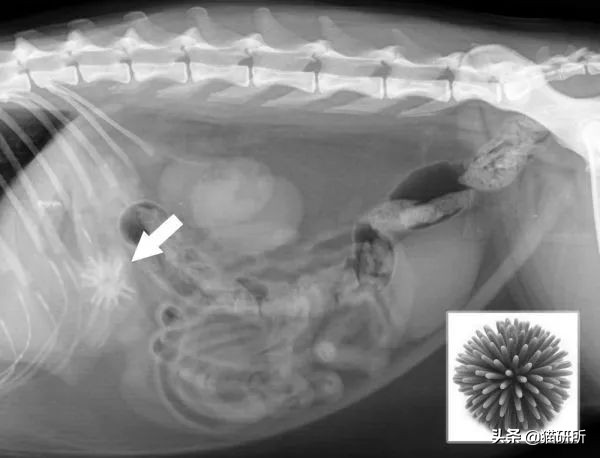

x光显示猫吞食玩具的病例,最后只能手术取出。图自:Gary Norsworthy